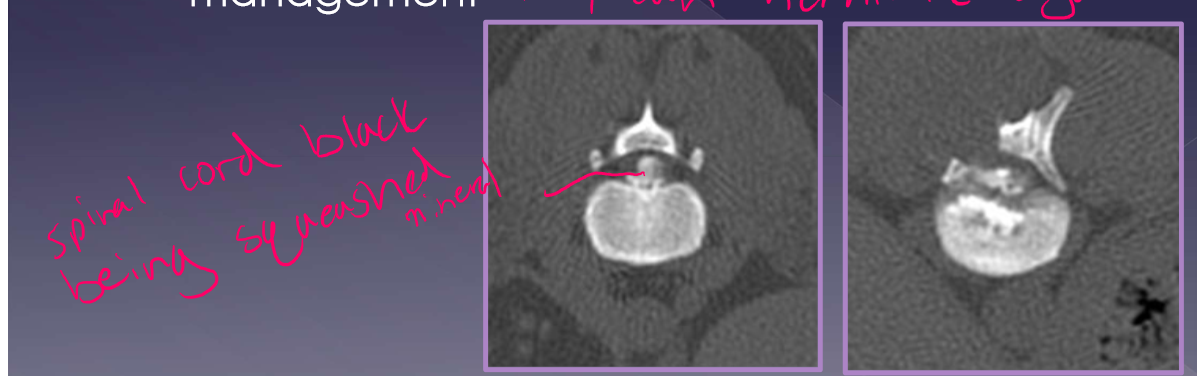

Disc-associated wobbler syndrome

middle-aged, large breed dog

Doberman pinscher*

vertebral canal stenosis (C5-6,6-7)

torsion of the caudal cervical

intervertebral disc protrusion

ligamentum flavum hypertrophy

osseous associated wobbler syndrome

young, giant breed, 9 ½ months old

Great Dane*

vertebral canal stenosis due to:

proliferation of the vertebral arch

articular process proliferation

pedicle proliferation

diagnosis

radiographs - limited information not helpful

CT -better for bone

traditional method

identify direction of compression

MRI * soft tissue better

gold standard

more accurate at identifying site, severity, nature of compression

assessment of spinal cord parenchyma

sometimes have to do MRI and CT